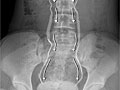

- Una pielografía intravenosa (IVP, por sus siglas en inglés) es una radiografía que muestra imágenes de las vías urinarias, incluyendo los cálculos renales.

- Una radiografía abdominal (de los riñones, de los uréteres y de la vejiga [KUB, por sus siglas en inglés]) proporciona una imagen de los riñones, de la vejiga y de los conductos que conectan los riñones con la vejiga (uréteres).

Cálculo renal visto en una pielografía intravenosa (IVP)